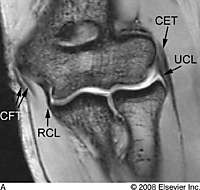

| Normal MRI anatomy. A, Normal coronal

anatomy. Coronal gradient-recalled-echo MR image illustrating the ulnar

collateral ligament (UCL), radial collateral ligament (RCL), common

flexor tendon (CFT), and common extensor tendon (CET).  |